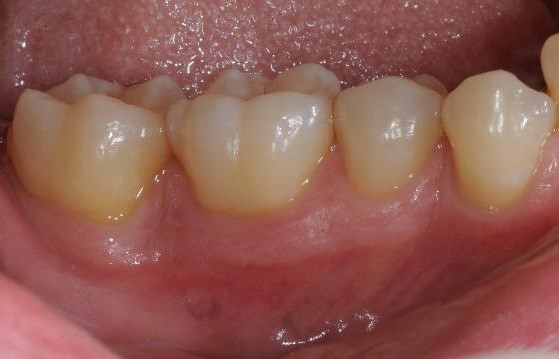

Radiographic view before periodontal regenerative therapy with Straumann® Emdogain®. A deep intrabony defect appeared mesially and distally on the left mandibular first premolar. Pre-surgical probing measured 8 mm. The defect morphology presented as well-contained.